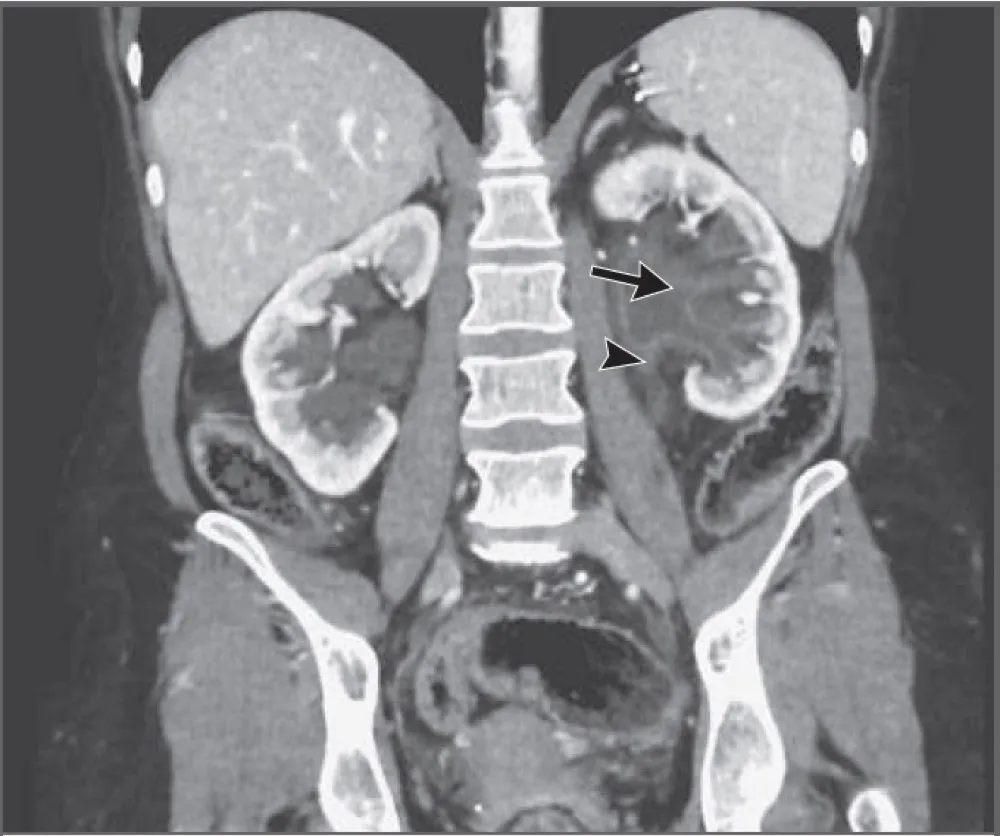

Uma causa incomum de hematúria glomerular intermitente!

Hematúria pós infecção, caso clínicos para auxiliar no entendimento de causas glomerulares comuns e raras...